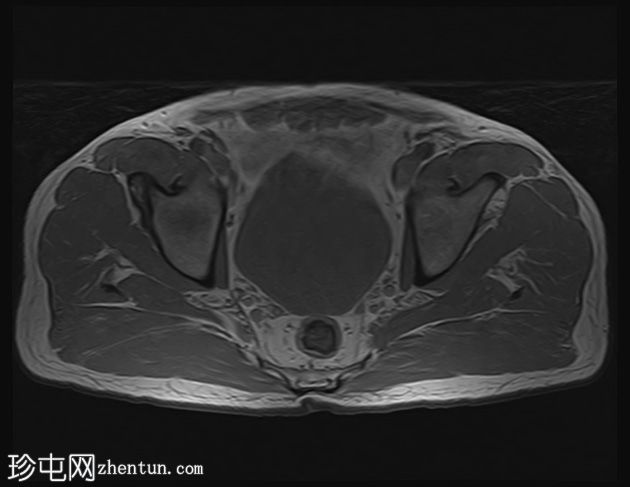

轴位

T2加权像

左侧股直肌近端至中段肌纤维内可见一长条状、边界清晰的肌内肿块,其大小约为:头尾径14.4 cm,横径6.6 cm,前后径2.7 cm。

该病灶在所有序列上均呈脂肪信号,T1加权像上呈高信号,脂肪抑制像上信号完全抑制(假性高信号)。

未见厚间隔、结节状结构或非脂肪成分。